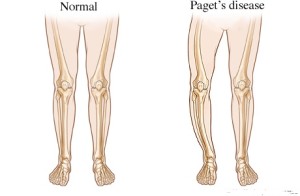

У многих больных наблюдается поражение костей именно в области позвоночника. Впрочем, иногда наблюдаются поражения и в костях черепа, а также таза. Симптомы болезни Педжета – сильная боль, деформация костей. Чаще всего, остеит возникает из-за переломов.

При возникновении данного заболевания обычно симптомов не наблюдается. Выявить точный диагноз сможет только доктор при рентгенологическом исследовании. При осмотре могут быть замечены выпуклый лоб или искривление ног. Из-за сильного кровотока в пораженных участках наблюдается покраснения, а также повышение температуры. Хоть данное заболеванием не протекает с воспалительным процессом, но его называют «деформирующим остеитом».

Обзор. Болезнь Педжета (PAJ-its) нарушает нормальный процесс регенерации костей в организме, при котором новая костная ткань постепенно заменяет старую. Со временем кости могут стать хрупкими и деформироваться. Чаще всего поражаются таз, череп, позвоночник и ноги.